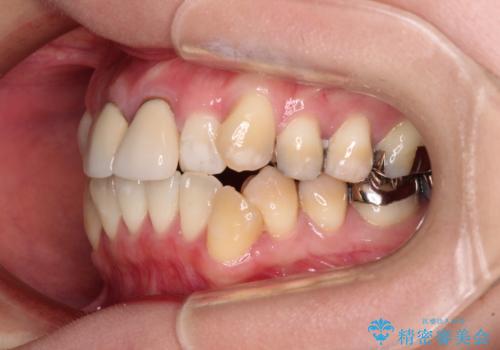

- 前歯のデコボコとセラミッククラウン周りの黒い縁を気にして来院された患者様です。

ワイヤー装置、マウスピース、どちらの装置でも治療は可能でしたが、マウスピース矯正の自己管理の煩わしさを懸念され、ワイヤー装置にて矯正治療を行うこととしました。

前歯の黒い縁は、矯正治療後にオールセラミッククラウンにて改善することとしましたが、いち早く目立たなくしたいとのことで、事前に矯正治療用仮歯に置き換えてから矯正治療を開始しました。